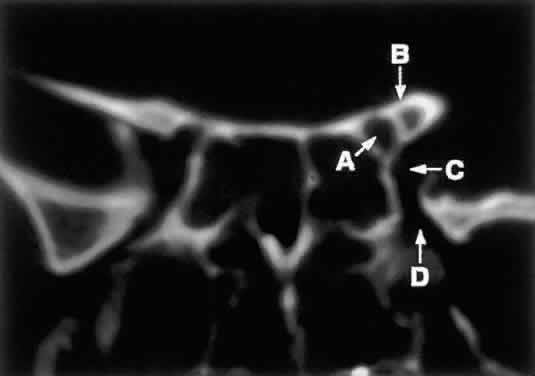

Radiographically, the spaces and foramina of the orbital apex may be considered to lie in three tiers (Fig. 8). The CS is found on the same level as the orbital apex, connecting directly with it via the superior orbital fissure (SOF) to form the middle tier. The inferior tier is formed by the inferior orbital fissure (IOF), which provides direct communication between the orbital apex and the pterygopalatine fossa, a vertically oriented space directly behind the maxillary sinus. Finally, the optic canal has no direct communication with any of the aforementioned spaces and should be considered to lie above the SOF and CS, exiting the orbit in a superomedial course through the body of the sphenoid as the superior tier.26 Orbital apical lesions can therefore gain ready access to the CS and pterygopalatine fossa (Fig. 9). Spread into the cranial vault through the optic canal is usually limited to lesions of the optic nerve (glioma) or nerve sheath (meningioma).

Fig. 8. Coronal CT image (bone window) of the orbital apex in a patient with facial trauma. Note the position of the posterior orbital foramina. The optic canal (A) is always seen in conjunction with the laterally adjacent anterior clinoid process (B) on both axial and coronal views. Slightly lower, the superior orbital fissure (C) communicates with the CS, found directly behind it. The inferior orbital fissure (D) provides communication through the orbital floor with the pterygopalatine fossa.